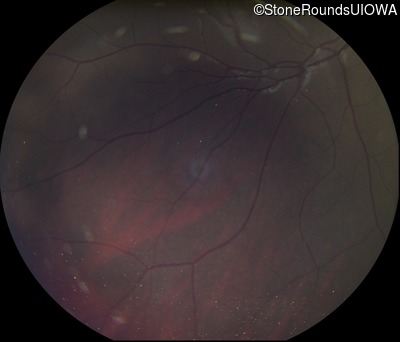

Fundus Photography - Right - 20/160 +1

Fundus Photography - Left - 20/125 -1

Optical Coherence Tomography - Right - 20/160 +1

Optical Coherence Tomography - Left - 20/125 -1